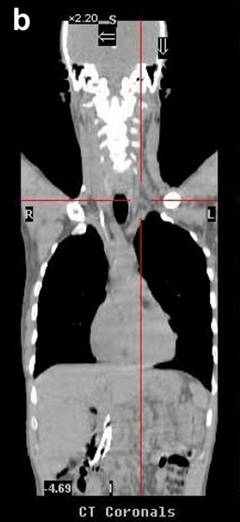

A 51-year-old Caucasian male presented with a history of progressive jaundice, loss of weight, acholic stools, and bilirubinuria. He was found to have a pancreatic head mass on a transabdominal ultrasound and CT scan of the abdomen. Fine needle aspiration cytology (FNAC) of the pancreatic mass confirmed well-differentiated ductal adenocarcinoma. The patient had unresectable disease given that the tumor encased approximately 180 degrees of the superior mesenteric artery. The initial CT scan of the abdomen showed nodules in the liver that were suspicious but not confirmatory for metastasis. Therefore, PET/CT scan was performed where no liver metastases were noted. CT scan of the neck did not demonstrate any evidence of supraclavicular metastasis (Figure 1). However, there was uptake of 18-fluorodeoxyglucose (FDG) with a standard uptake value (SUV) of 4.3-4.7 in the medial left supraclavicular region that was suspicious for nodal metastasis (Figures 2 and 3). FNAC of the left supraclavicular lymph node showed poorly differentiated metastatic adenocarcinoma consistent with a pancreatic primary. Therefore, the final clinical staging was stage IV (T4NXM1, Table 1).

Figure 2. PET scans of Patient #1 before (a.) and after (b.) chemotherapy showing supraclavicular metastasis. |

Figure 3. PET/CT scans of Patient #1 before (a.) and after (b.) chemotherapy showing supraclavicular metastasis. After 5 cycles of chemotherapy, PET/CT scan (b.) shows favorable response to therapy with decrease in SUV of supraclavicular lymph nodes from 4.3-4.7 (baseline, a.) to 2.4 (b.). |

After confirmation of metastatic disease, the patient was started on gemcitabine 1,000 mg/m2 and nab-paclitaxel 100 mg/m2, both intravenously (i.v.) on days 1, 8, and 15 with cycles repeated every 28 days. At the most recent presentation, the patient had completed five cycles of systemic chemotherapy with gemcitabine and nab-paclitaxel. His CA 19-9 level had declined from 962 U/mL at baseline to 444 U/mL (reference range: 0-55 U/mL) and his PET/CT and CT scans demonstrated a favorable response to therapy. Notably, his PET/CT scan showed a decrease in SUV in the left supraclavicular nodal metastasis from 4.3-4.7 at baseline to 2.4 (Figure 3).

In all of the three cases reported in this article, PET/CT scans detected supraclavicular lymph node involvement that was not identified by the standard imaging protocol, CT scan of the chest and abdomen, for pancreatic cancer. Of note, CT scans, which are the de facto surveillance imaging modality, failed to detect metastasis in all three cases (Figure 1). Of course, this was predominantly due to the fact that CT scans of the neck would not be part of a routine surveillance algorithm for patients with pancreatic cancer.